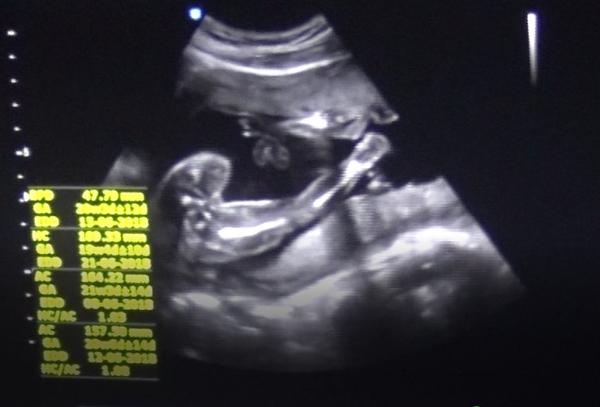

@mariejosef Díky za tip, já pořád přemýšlím, zda to jsou kulky či kávové zrno... pindíka jsem tam vysloveně na videu (mám nahrané) neviděla, ale určitě hodně závisí na úhlu... v 21t pořád netuším, co to bude (moji doktoři nejsou sdílní, když nevidí peníze) 🙂

@daasqua ti to jsou Dr Teda hrůza 😥